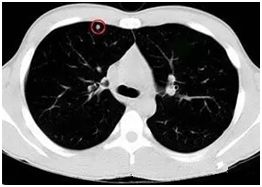

●高危結(jié)節(jié)

●結(jié)節(jié)呈毛栗子樣,周圍有角(棘突)和細(xì)小毛刺生長(zhǎng)

●結(jié)節(jié)如月亮,周圍有一圈暈

●結(jié)節(jié)呈分葉狀

●多位于上葉結(jié)節(jié)

●結(jié)節(jié)里有較粗的血管牽扯進(jìn)來(lái)

●結(jié)節(jié)里有透亮的小空泡(空氣支氣管征)

●結(jié)節(jié)外圍有胸膜牽拉征象(臍凹征)

●隨訪3—6月以上,結(jié)節(jié)明顯增大或內(nèi)部密度增高

對(duì)于以上的高危結(jié)節(jié)應(yīng)由胸外科、腫瘤內(nèi)科、呼吸科和影像醫(yī)學(xué)科醫(yī)生集體會(huì)診,決定是否需要進(jìn)一步檢查(包括支氣管鏡、CT增強(qiáng)掃描、經(jīng)皮穿刺活檢等)明確診斷,以及采取什么方法治療。

對(duì)高度懷疑為惡性者且適合于外科手術(shù)者,首選手術(shù)治療。對(duì)肺癌可能性小的病例可抗炎治療7—10天,休息一周后復(fù)查,結(jié)節(jié)增大或無(wú)變化,可進(jìn)入臨床治療,結(jié)節(jié)縮小可動(dòng)態(tài)隨訪。